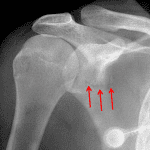

- Acute nondisplaced scapular fracture with extension into the inferior glenoid

- Scapula fracture

Acute nondisplaced scapular fracture with extension into the inferior glenoid.

No joint malalignment.

Patchy right midlung airspace opacification, which may represent pulmonary contusion. Recommend correlation with dedicated chest imaging.